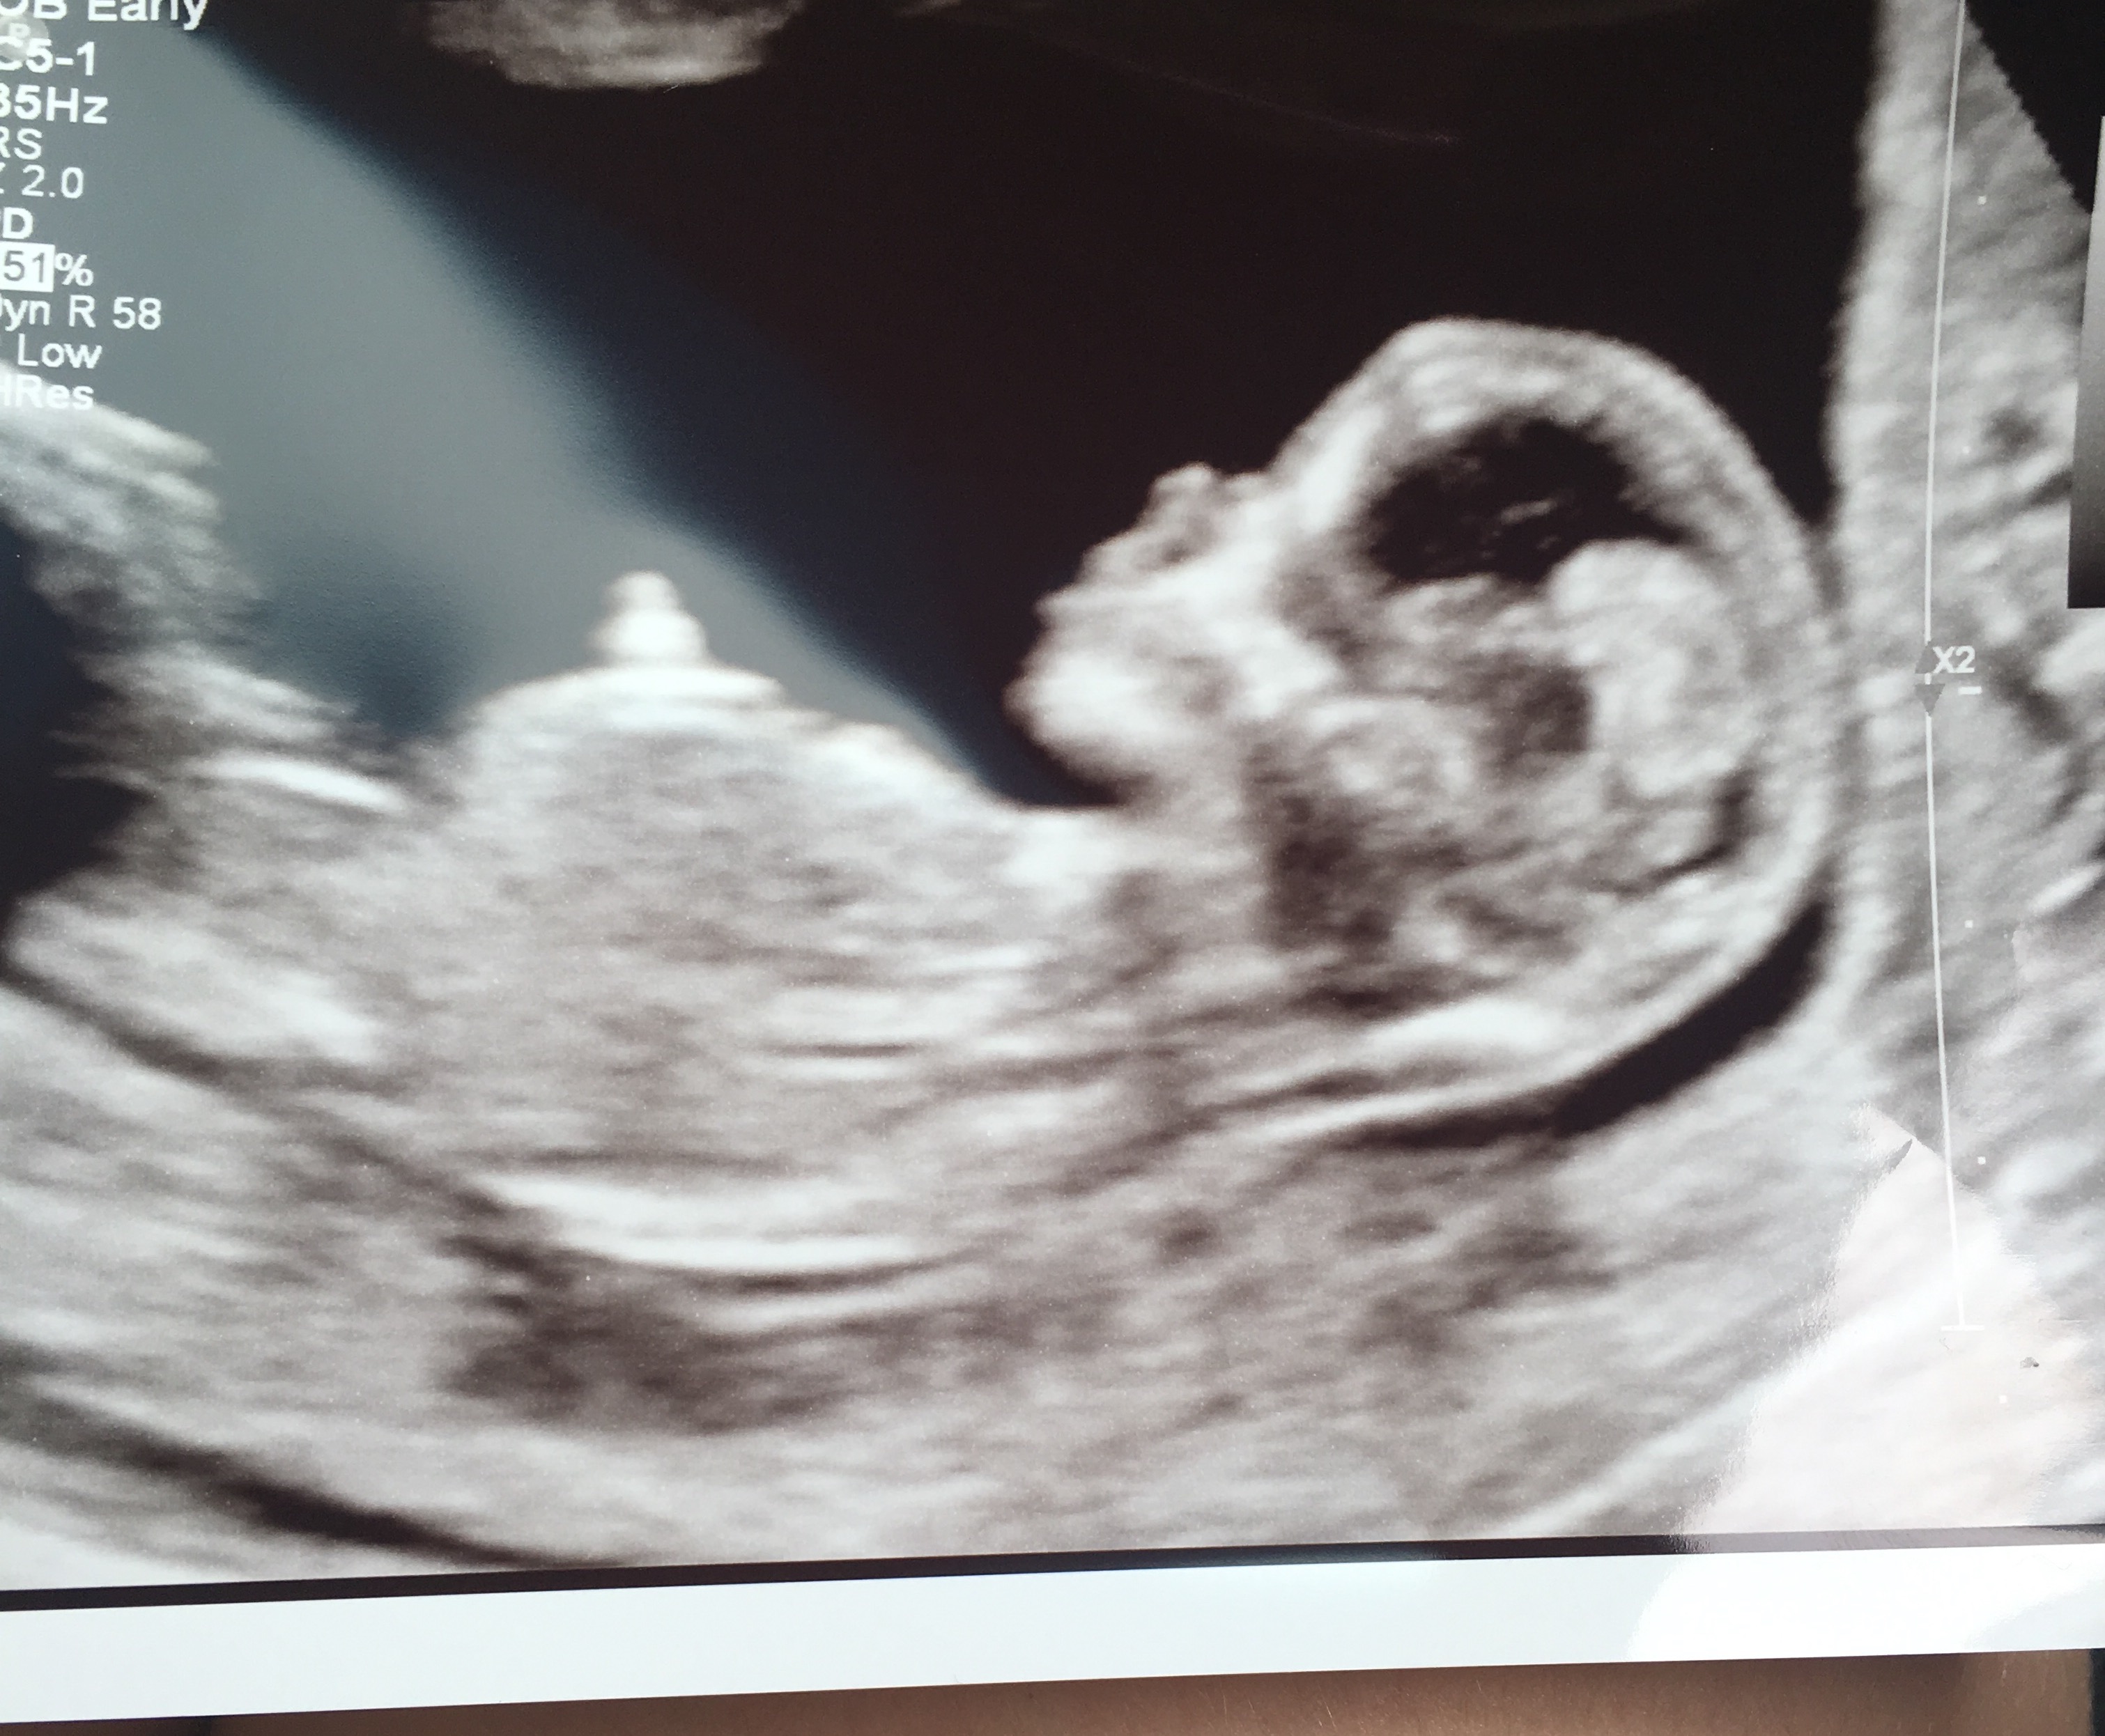

boy or girlll!! due January 20, 2017. i am 13 1/2 weeks!